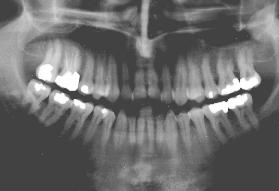

X-ray of Sten-Anders Fellman